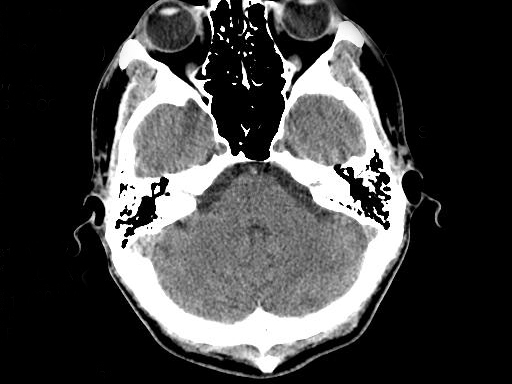

A Ischemic Stroke Shown As Dark Black Area B Hemorrhagic Download Scientific Diagram